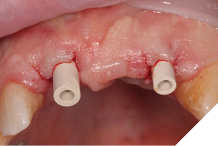

Small H-shaped incisions were made over the implant fixtures to enable access to position Mono-Scan bodies to allow a digital 3 shape scan of the implants in situ in relation to each other, adjacent and opposing teeth. We then planned to fabricate a provisional bridge to develop aesthetic soft tissue profiles (Figs. 22-24).

Fig. 22

Fig. 23

Fig. 24